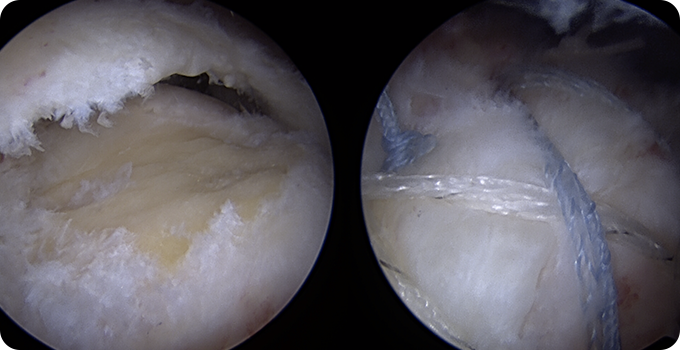

회전근개파열의 여러 모습들

기존의 삼각근을 절개하고 회전근개를 노출시켜서 수술하는 방법이 아닌 초소형 카메라인 관절내시경을 삼각근을 통과시켜 회전근개파열을 봉합합니다. 힘줄 주변의 근육 손상을 최소화시킬수 있기 때문에 수술 후 유착 반응이나 통증 반응이 감소하여 빠른 재활이 가능합니다.